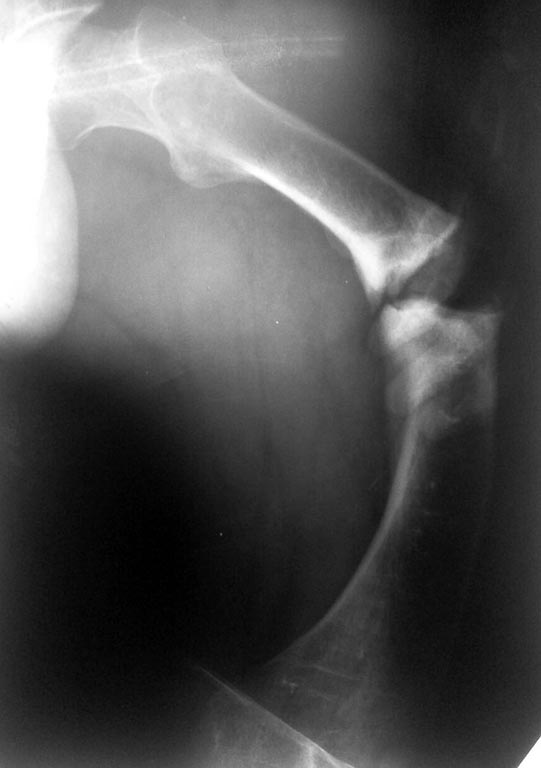

Помогите разобраться с переломом бедра у непростого пациента.

Молодой пациент (абсолютно социален и адекватен), рост около 140 см,

бедро 20 с небольшим, по механической оси. Низкоэнергетическая травма,

судя по записям в амбулаторной карте - несколько раз оперировался по

поводу болезни Блаунта в детстве на голенях, сведений и следов

операций на бедрах нет. Рассматриваем несколько вариантов остеосинтеза:

3. ЧКО Нужно ли резецировать зону перелома при последних двух вариантах

(выглядит как псевдоартроз)? Любые соображения, варианты приветствуются,

сожалею за снимки, лучше не получилось.